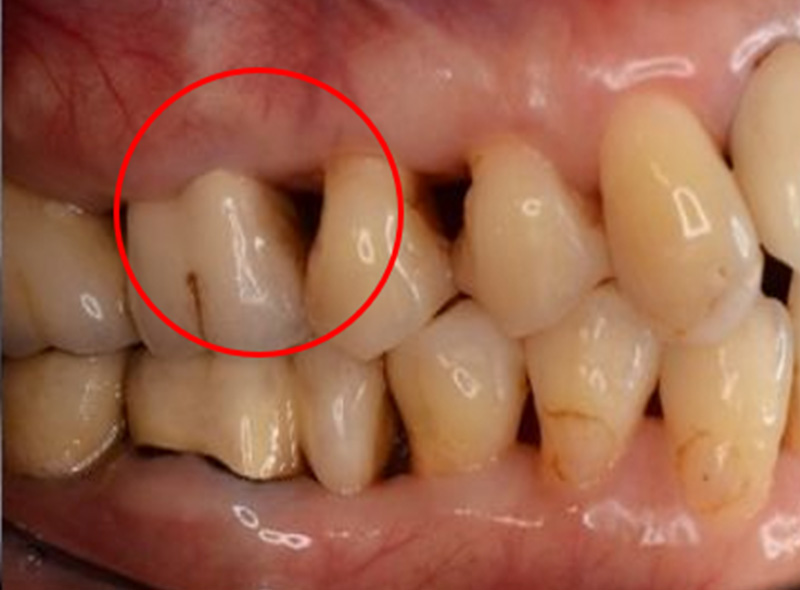

根分岐部病変

(根が分岐している奥歯に生じた歯周病)

の治療

~専門医・指導医による歯周病治療3~

治療の概要

根分岐部病変は、歯根が2本以上ある歯の根分岐部まで進行した歯周病で、歯石除去が難しくブラッシングもしにくい場所のため、症状が出にくく治療が難しいのが特徴です。歯周病を制するには根分岐部病変を制する必要があり、進行した場合は抜歯の選択肢が検討されることも少なくありません。

さっさと抜いてインプラント、ではなく、根分岐部病変をどう考えてどう生かすかが歯周病専門医の姿勢や力量です。

治療例の紹介